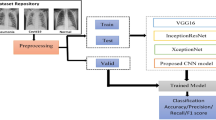

New potential for healthcare has been made possible by the development of the Internet of Medical Things (IoMT) with deep learning. This is applied for a broad range of applications. Normal medical devices together with sensors can gather important data when connected to the Internet, and deep learning uses this data to reveal symptoms and patterns and activate remote care. In recent years, the COVID-19 pandemic caused more mortality. Millions of people have been affected by this virus, and the number of infections is continually rising daily. To detect COVID-19, researchers attempt to utilize medical imaging and deep learning-based methods. Several methodologies were suggested utilizing chest X-ray (CXR) images for COVID-19 diagnosis. But these methodologies do not provide satisfactory accuracy. To overcome these drawbacks, a recalling-enhanced recurrent neural network optimized with golden eagle optimization algorithm (RERNN-GEO) is proposed in this paper. The intention of this work is to provide IoT-based deep learning method for the premature identification of COVID-19. This paradigm can be able to ease the workload of radiologists and medical specialists and also help with pandemic control. RERNN-GEO is a deep learning-based method; this is utilized in chest X-ray (CXR) images for COVID-19 diagnosis. Here, the Gray-Level Co-Occurrence Matrix (GLCM) window adaptive algorithm is used for extracting features to enable accurate diagnosis. By utilizing this algorithm, the proposed method attains better accuracy (33.84%, 28.93%, and 33.03%) and lower execution time (11.06%, 33.26%, and 23.33%) compared with the existing methods. This method can be capable of helping the clinician/radiologist to validate the initial assessment related to COVID-19.